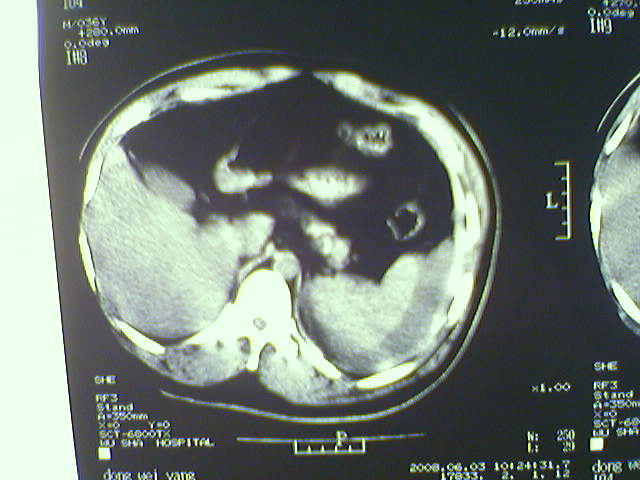

以下是引用zjzjr在2008-6-3 21:01:00的发言:[br]腹腔积液+邻近软组织肿厚.考虑感染性病变可能性大.